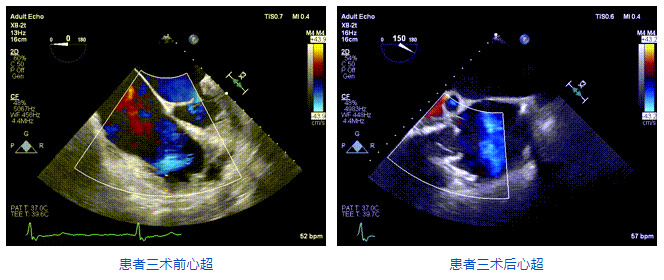

2021年12月24日,復(fù)旦大學(xué)附屬中山醫(yī)院葛均波院士團(tuán)隊(duì)成功應(yīng)用LuX-Valve Plus為一例極重度三尖瓣反流(TR)合并房顫、房缺的患者完成了經(jīng)血管三尖瓣置換術(shù),這是在前基礎(chǔ)上,本周完成的第三例經(jīng)血管三尖瓣置換手術(shù),葛均波院士、周達(dá)新教授等與心外科魏來教授、賴顥教授,心超室的潘翠珍教授、李偉教授及麻醉科的郭克芳教授共同完成了本周手術(shù),均獲得圓滿成功!患者術(shù)后超聲顯示無TR,臨床癥狀明顯改善。本周手術(shù)的成功也為LuX-Valve Plus救治性臨床研究添上了濃墨重彩的一筆。

三例患者入院后,葛均波院士團(tuán)隊(duì)周達(dá)新教授、潘文志教授、張?jiān)床┦?、陳莎莎博士及心超室的潘翠珍教授、李偉教授對患者的情況進(jìn)行詳細(xì)評估和討論,最終決定為三例患者選擇LuX-Valve Plus40mm、50mm和50mm型號(hào)的瓣膜進(jìn)行手術(shù)治療。手術(shù)后即刻拔除氣管插管,術(shù)后患者三尖瓣反流癥狀得到顯著改善,復(fù)查心超結(jié)果顯示人工三尖瓣瓣膜支架固定穩(wěn)定,瓣葉關(guān)閉形態(tài)未見異常,未見明顯反流。